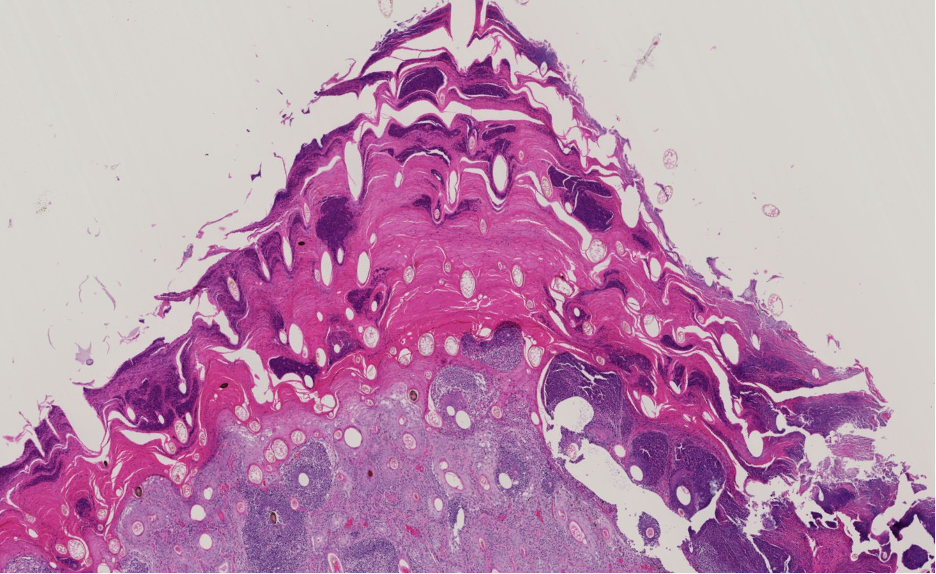

How does orf present grossly?

Typical pox lesion around lips, muzzle and eye showing great degree of epidermal proliferation and crust

How does orf present histologically?

Spongiosis

Micropustules

Epidermal hyperplasia

Intra-cytoplasmic inclusion bodies